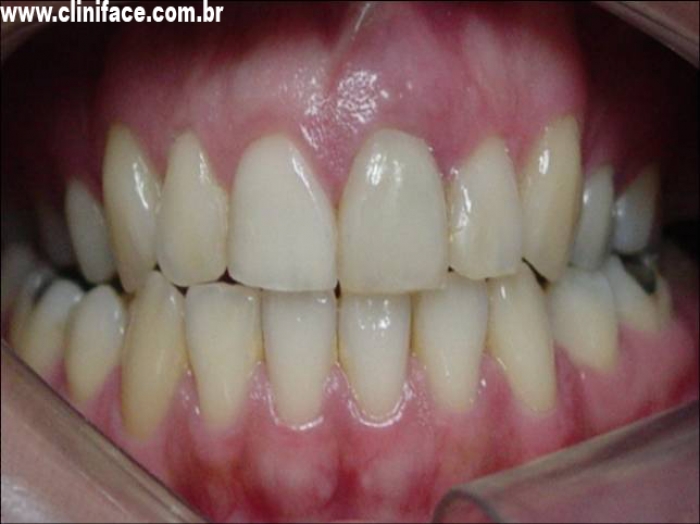

Sorriso inicial